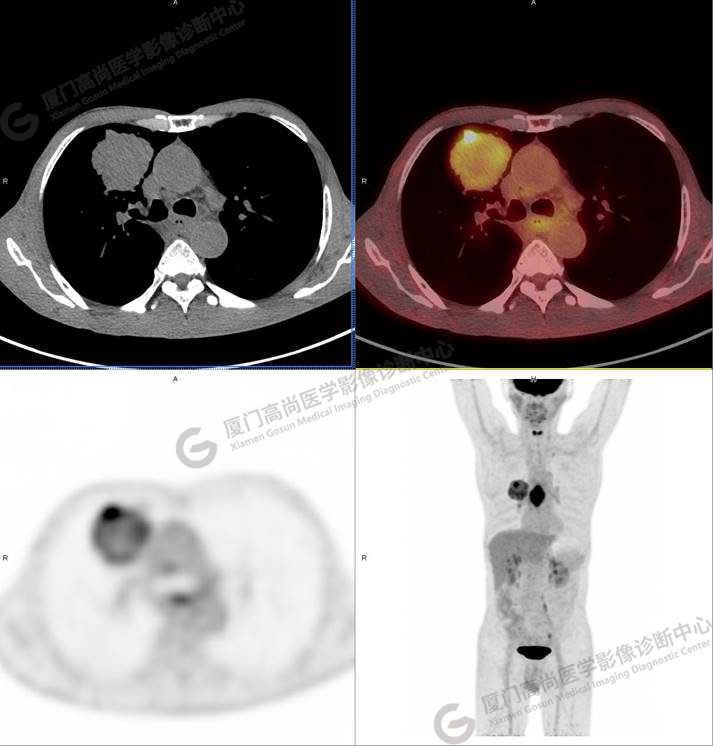

右肺上葉軟組織密度腫塊,大小約5.9×5.5×6.3cm,形態(tài)不規(guī)則,邊緣見棘突,其內(nèi)密度不均勻,放射性攝取不均勻性增高,SUVmax 6.46;腫塊周圍見多發(fā)小結(jié)節(jié)影,較大者直徑約0.6cm,放射性攝取未見明顯增高。影像學(xué)表現(xiàn)考慮右肺癌并肺內(nèi)轉(zhuǎn)移。

同時(shí)發(fā)現(xiàn)食管中段管壁增厚,管腔狹窄,放射性攝取不均勻性增高,SUVmax 9.67。